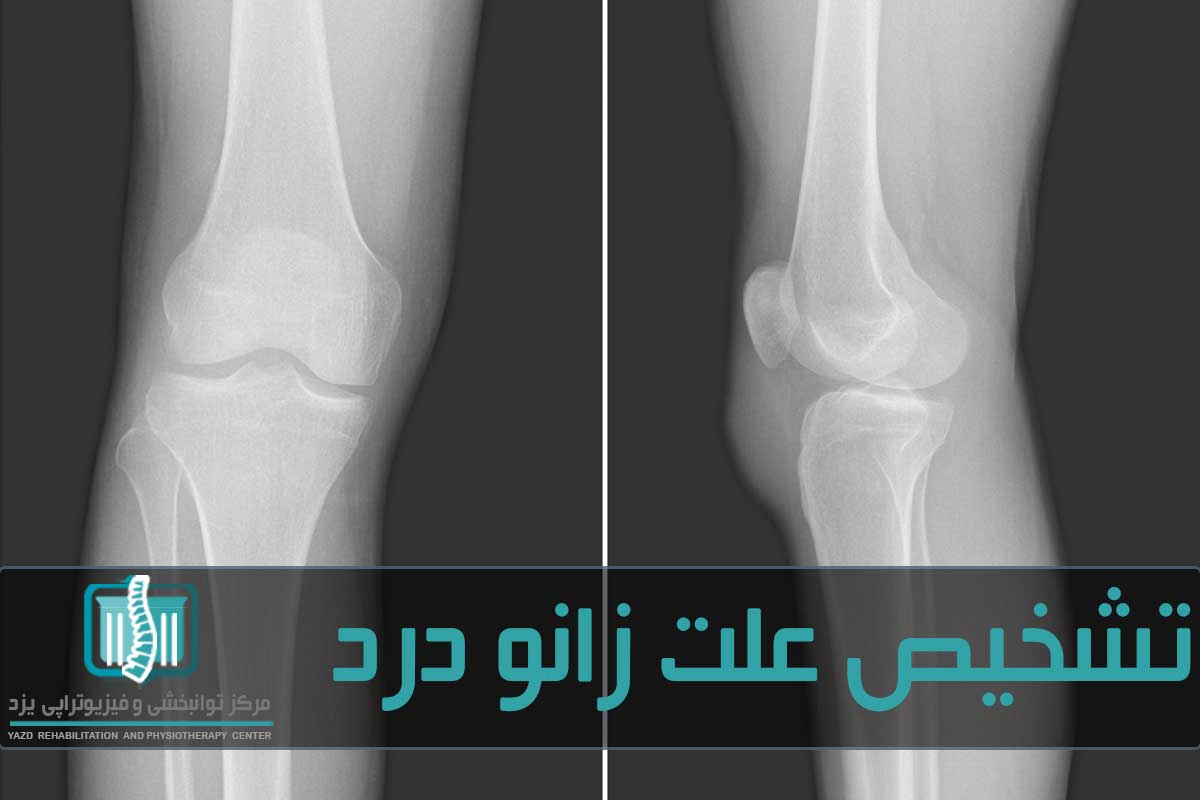

در مرحله بعد ارزیابی زانو انجام میشود. ارزیابی شامل خمکردن زانو به اندازه دامنه حرکتی، بررسی ثبات رباطها و هرگونه حساسیت و تورم است. معمولاً پزشک زانوی دردناک را با زانوی دیگر مقایسه میکند. گاهی اوقات ممکن است پزشک برای تشخیص دقیق آزمایشات زیر را تجویز کند: